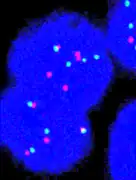

Her2 and Her3 distribution on a breast cell, (3D Dual Colour Super Resolution Microscopy SPDMphymod / LIMON, marked with Alexa 488 and 568)